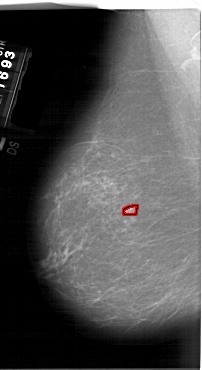

FILE: A_1549_1.LEFT_CC.OVERLAY

TOTAL_ABNORMALITIES 1

ABNORMALITY 1

LESION_TYPE MASS SHAPE OVAL MARGINS ILL_DEFINED

ASSESSMENT 4

SUBTLETY 2

PATHOLOGY BENIGN

TOTAL_OUTLINES 1

BOUNDARY